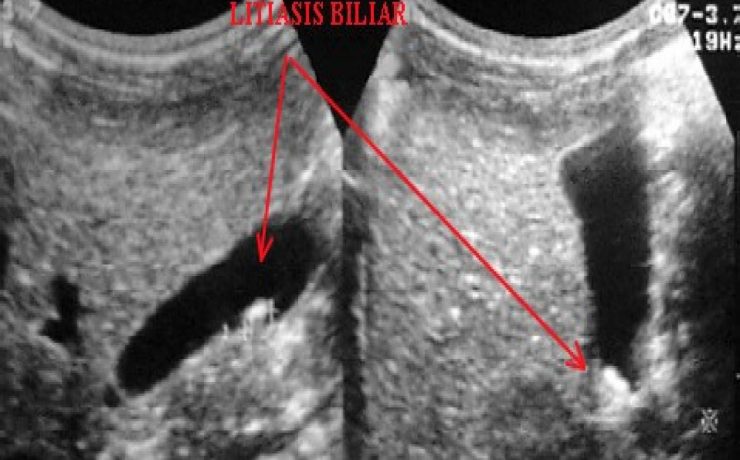

Se realizó un estudio descriptivo prospective, evaluando a 336 pacientes operados de colecistitis aguda o crónica por vía laparoscópica. Todos los pacientes fueron evaluados con ecografía abdominal al menos 7 días antes de la cirugía por un médico radiólogo experto y de acuerdo a varios parámetros se dividen en 3